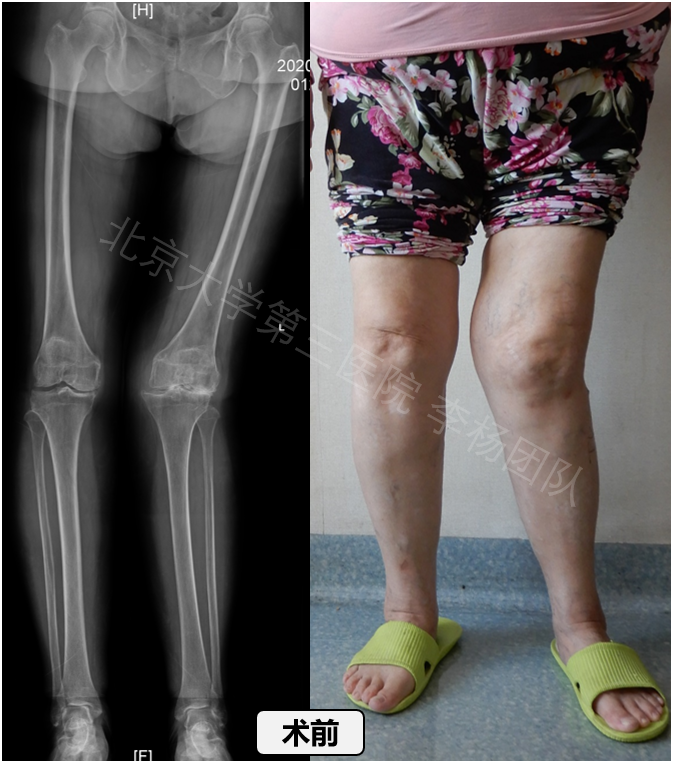

为此脊髓灰质炎后遗症期的软组织矫形手术适用于什么患者,有关其后遗症的医治文献亦急剧消失。目前,我国大规模流行已得到控制,但散在流行仍时有发生。我国是世界脑干灰质炎后遗症病人最多的国家,据国家残障人抽样调查脊髓灰质炎后遗症期的软组织矫形手术适用于什么患者,全省约有183万。近20年来,我国医务工作者对其医疗与复健做了大量的研究工作,我国的医疗水平代表着世界的研究水平。脑干灰质炎后遗症腿部最常见。据北京二医附属新华诊所统计[1],在救治的4856例中,进行9494次各类不同放疗,其中膝周围放疗占30%左右。解放军第208诊所在统计的8427例次放疗中,脚部矫形放疗2564例次,约占1/3[2]。膝关节是四肢最大结构最复杂的关节,是上肢运动的枢纽,是恢复四肢持重功能的关键部位。现将近年来有关脑干灰质炎后遗膝关节畸形矫正临床研究与实验研究的国外外进展综述如下。file:///E|/qk/xdkf//0001/.htm(第1/5页)2010-3-2311:06:26万方数据